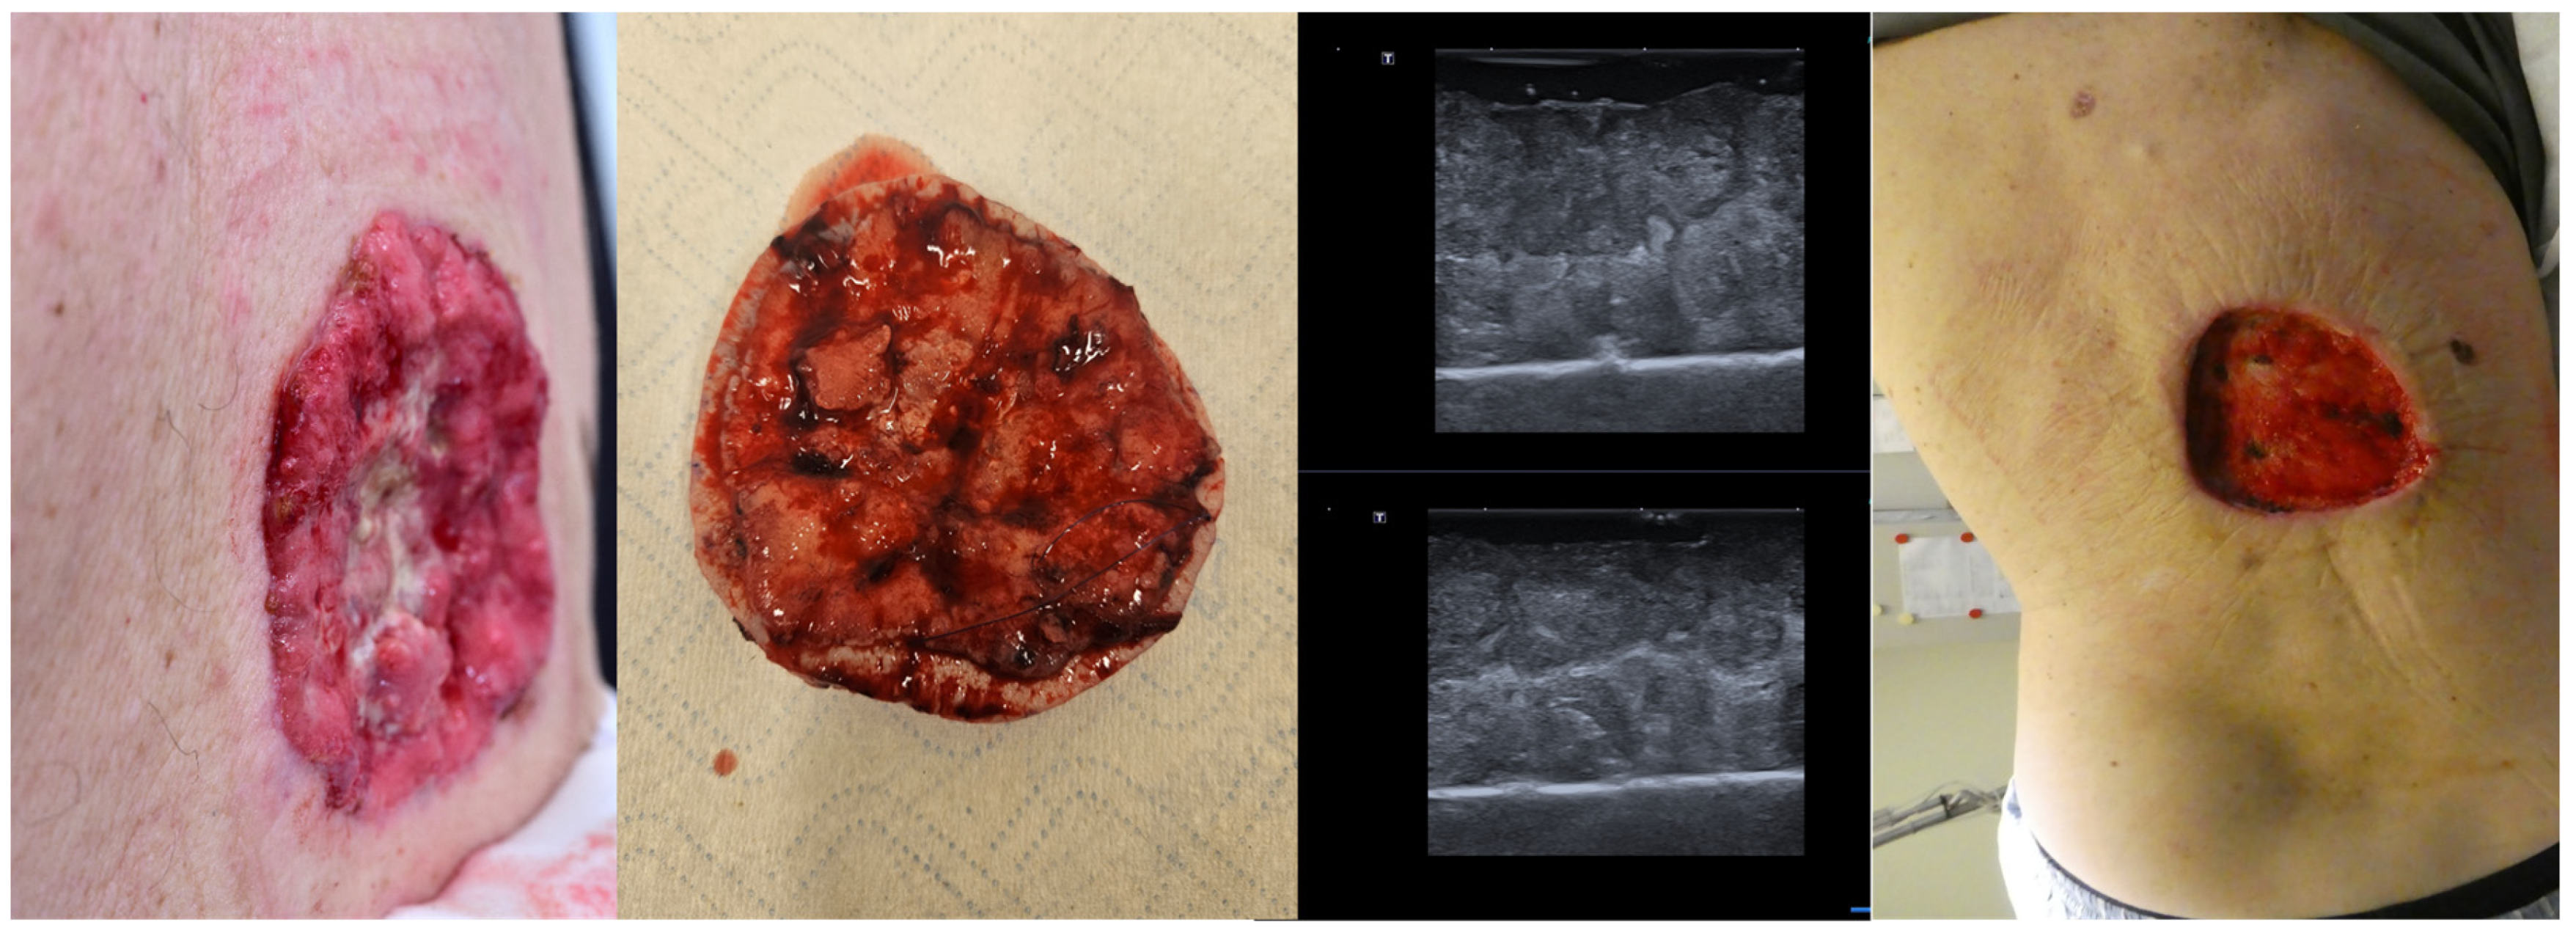

9. Ex Vivo Tumor Margin Assessment

10. Avoidance of Unnecessary Surgeries due to Patient Up-Staging

11. Intraoperative Guidance